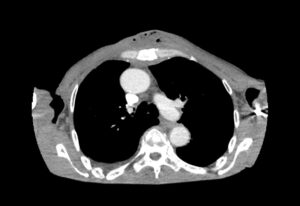

Chest wall abscess, CT axial, unannotated. JETem 2024

Chest wall abscess CT axial unannotated. JETem 2024